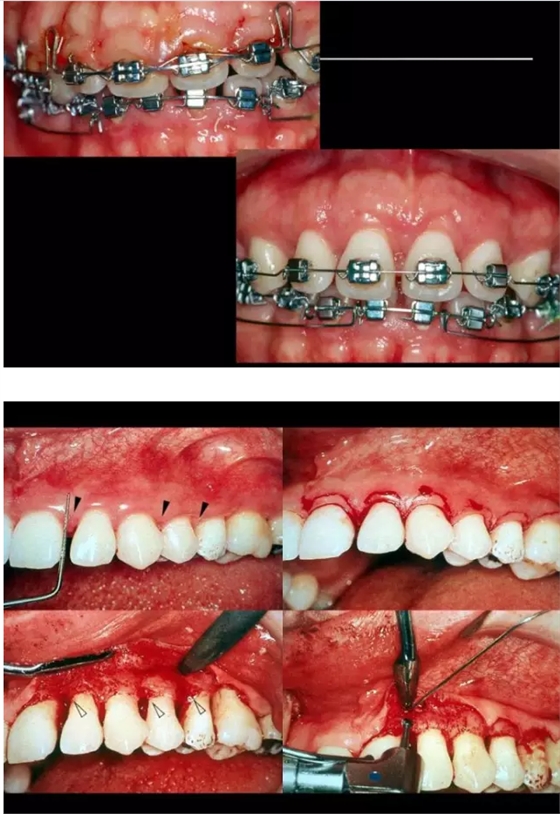

【牙科知識(shí)】牙周病相關(guān)手術(shù)圖解,非醫(yī)學(xué)專業(yè)勿點(diǎn)